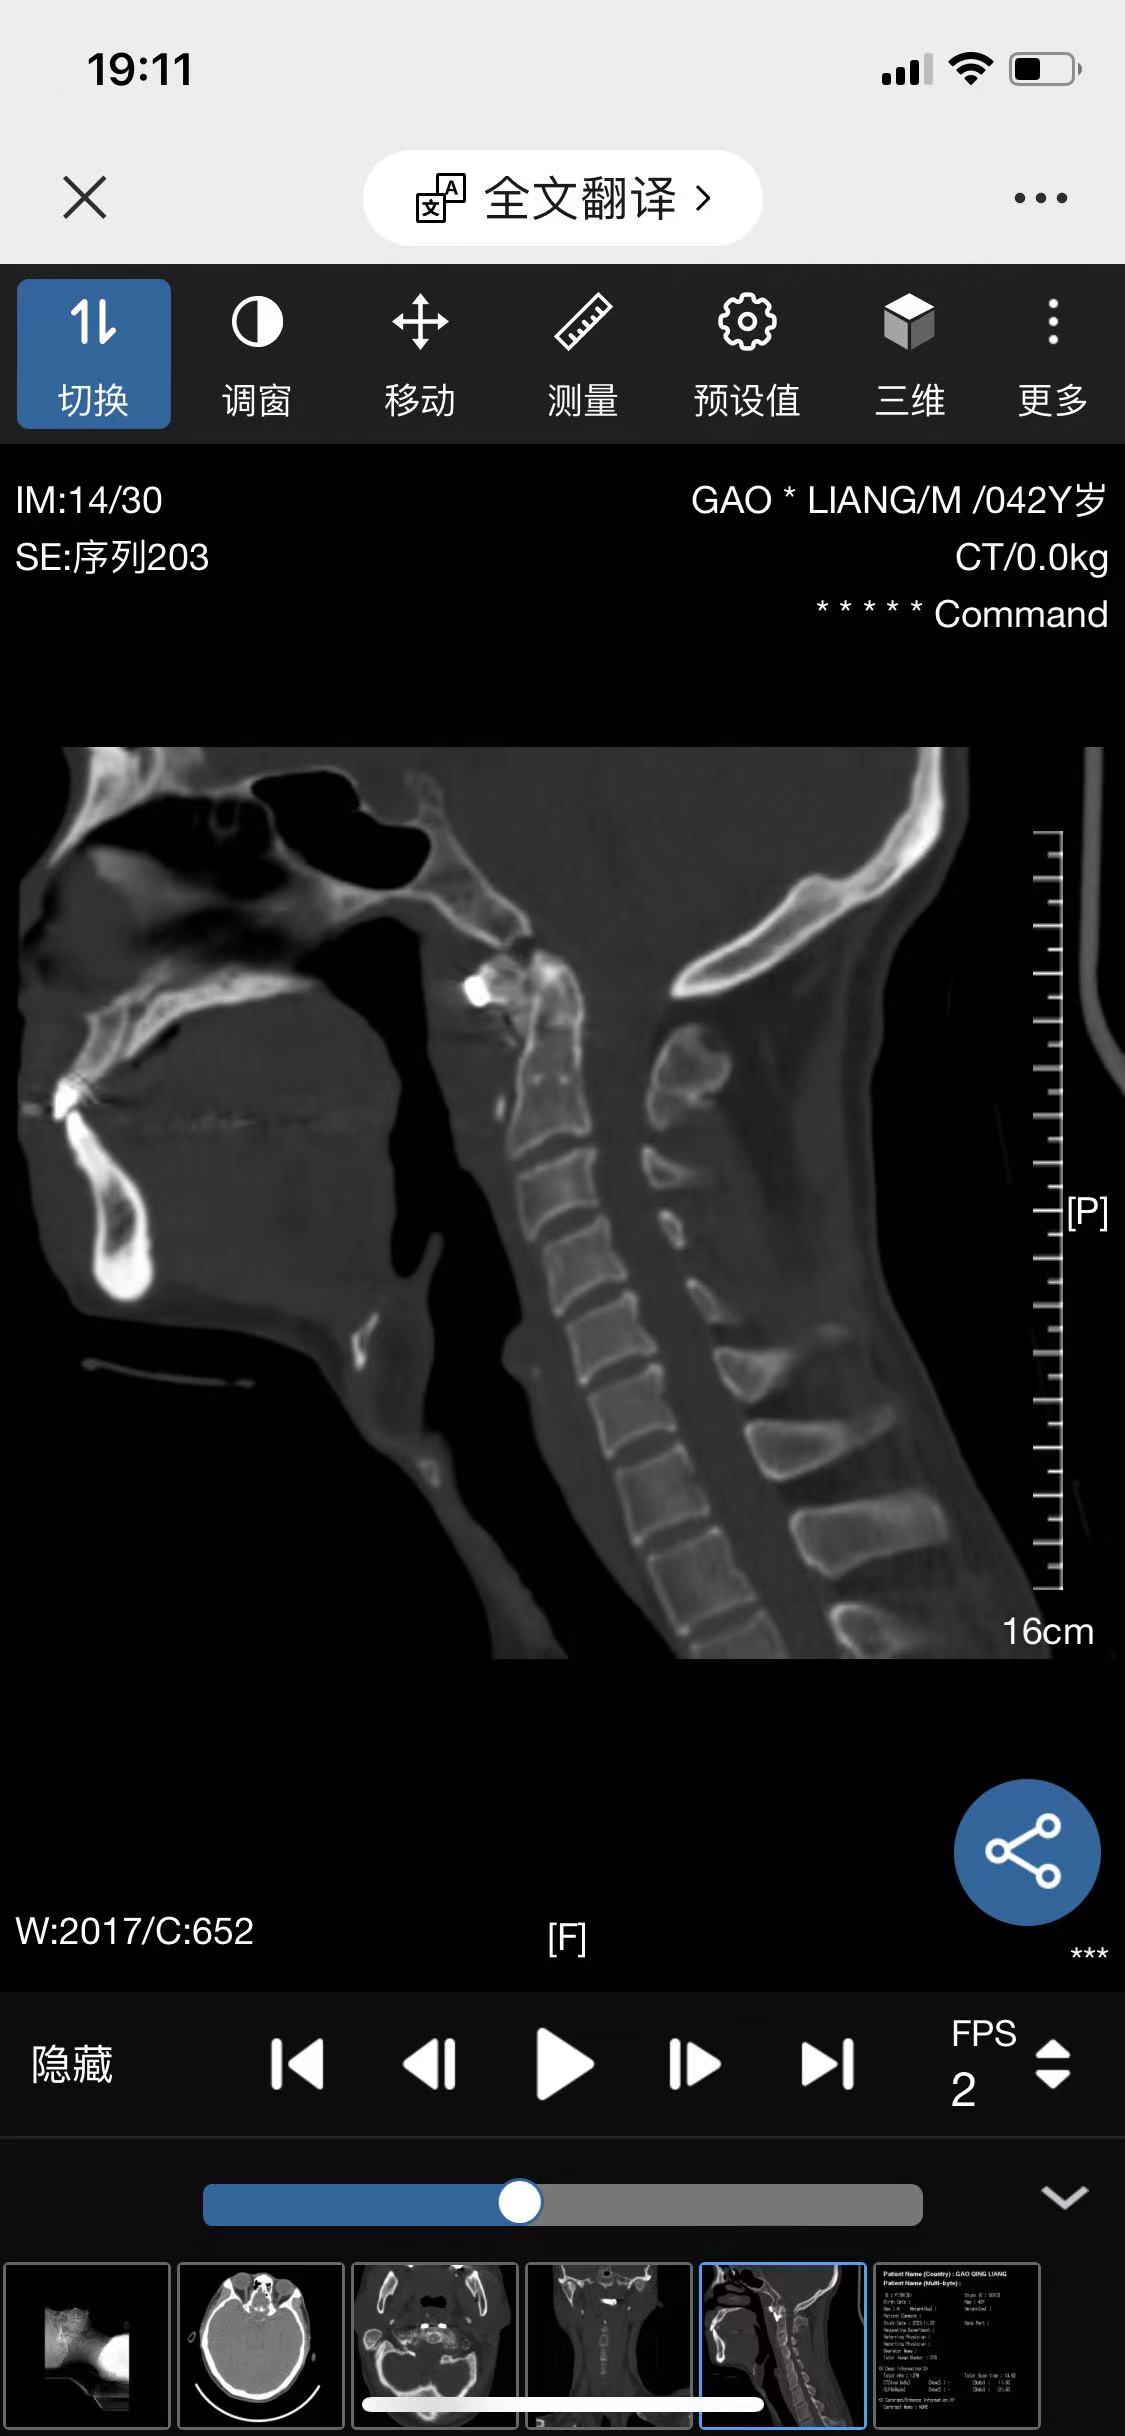

• 诊断:寰枢椎脱位

• 影像:

• 术后影像: